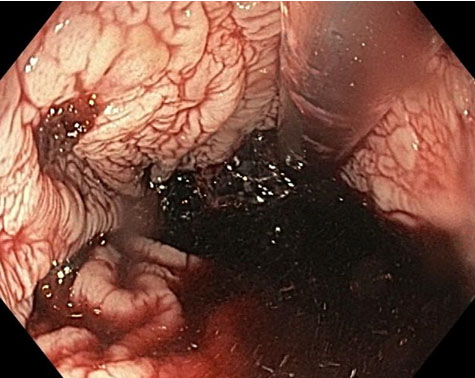

Gastroscopy was done under general anesthesia. In this procedure a gastroscope (GIF-H190; Olympus, Center Valley, PA, USA) and an esophageal overtube were used (Guardus Overtube; Steris, Mentor, OH, USA). Gastroscopy found a large amount of food bolus and blood clot in the dilated esophagus precluding further advancement of the gastroscope. The gastroscope was removed, and an overtube was fitted. The scope and overtube were then reinserted via the mouth and advanced to the esophagus to facilitate repeated passages of the scope. There was a large amount of organized clot and food in the entire esophagus. Due to this scope passage to the lower esophagus was not possible. Large clots with food were snared, suctioned, and manipulated to allow reasonable capture in repeated Roth Net passes (Figure 1). A combination of endoscopic suction, irrigation, snare use, and Roth Net use provided little improvement in clearance. Hence a nasogastric (NG) tube was inserted via the overtube into the oesophagus under direct visualization being following by the gastroscope (Figure 2). With adequate lubrication, the overtube can easily accommodate the standard gastroscope and an NG tube (Figure 3). The NG tube was connected to wall suction. The NG tube can be manipulated back and forth controlled at the site of insertion in the overtube to ensure adequate and—to some degree—targeted suction. With a combination of endoscopic irrigation and direct high suction with the NG tube, the food and clot were broken down and cleared effectively.

Figure 1: Endoscopic image showing a mixture of food and clots in the dilated esophagus.